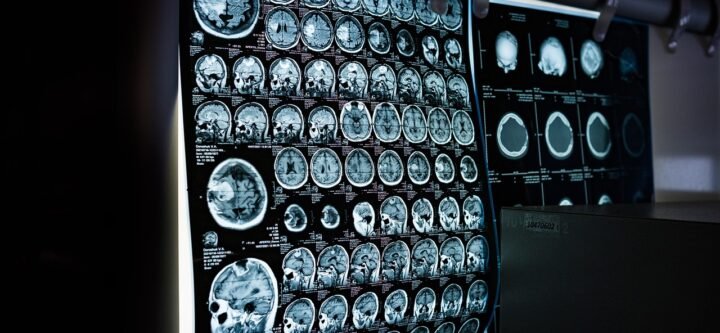

المختبر الطبي في مركز سِتي كير الطبي، يقدم مختبرنا المتطور مجموعة واسعة من التحاليل المخبرية لدعم صحتك ورفاهيتك. نوفر اختبارات الدم الكامل (CBC) لتقييم الصحة العامة، بالإضافة إلى اختبارات سكر الدم وملف الدهون للمساعدة في اكتشاف مرض السكري وتقييم مخاطر أمراض القلب. تضمن اختبارات وظائف الكبد والكلى أداء أعضائك الحيوية…